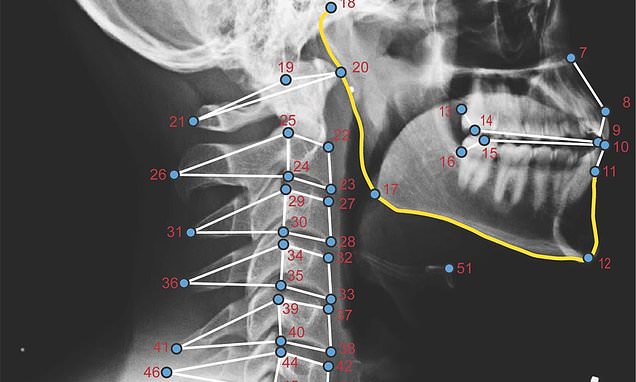

To see how electronic devices affect posture, the US

researchers X-rayed 10 women and 12 men while they used a tablet in five

different positions.

But the X-rays, which researchers marked with the six

vertebrae in the neck and another 46 stress points in the face and jaw, did

show a difference when people sat upright, bent fully forward or reclined at 15

or 30 degrees.